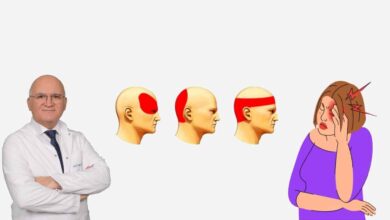

Sinir sıkışmasının belirtilerini biliyor musunuz?

Sinir sıkışması sonucunda ağrı belirleyici bir özelliktir. Bazı sıkışmalarda ise ağrı ortaya çıkmayabilir. Sinir sıkışması parmaklarda uyuşma ve karıncalanma, kavrama işlemi sırasında güçsüzlükle kendini belli etmektedir. Ayrıca, sıcak ve soğuktan aşırı etkilenme, kaslarda kuvvetsizlik ve terleme bozuklukları ortaya çıkabilmektedir.

- Geceleri uykudan uyandıran el uyuşması,

- Sinir sıkışmasının görüldüğü bölgedeki ödem,

- Sıkışmasının olduğu bölge boyunca ortay çıkan ağrı ya da sızı,

- İlerlemiş durumlarda güç kaybı.

- Hareket ederken kaslarda katılık

- El ve parmaklarda karakteristik deformasyonlar